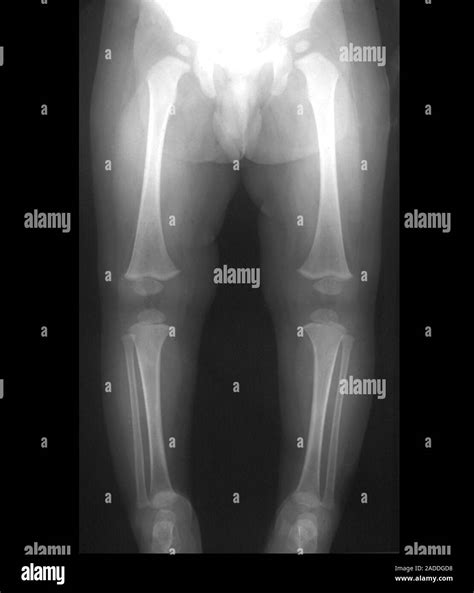

Infant X-ray imaging involves the use of low-dose radiation to produce images of the internal body structures. This technique is particularly useful for diagnosing conditions such as fractures, pneumonia, and congenital anomalies. The process is quick and relatively painless, making it suitable for infants who may be too young to cooperate with more complex diagnostic procedures.

• Early Detection of Fractures: X-rays can quickly identify fractures, which is essential for prompt treatment and recovery.

Fractures X-rays can identify fractures in bones, which may result from accidents or underlying conditions like osteoporosis.